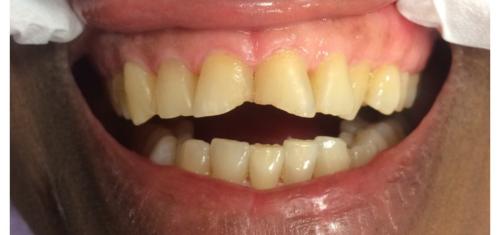

Before / After

From stained or misaligned teeth to a radiant, confident smile, our results speak for themselves. See the difference professional dental treatment can make — and imagine what we can do for you.

Teeth Whitening